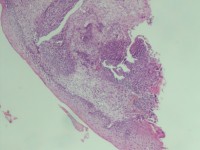

性别

女

年龄

43岁

临床诊断

宫颈病变

一般病史

宫颈癌筛查:hpv16(+))

标本名称

宫颈组织

大体所见

灰白色组织

老师们看看,高级别累腺吗

高级别累腺,不除外局灶早期浸润

高级别累及腺体